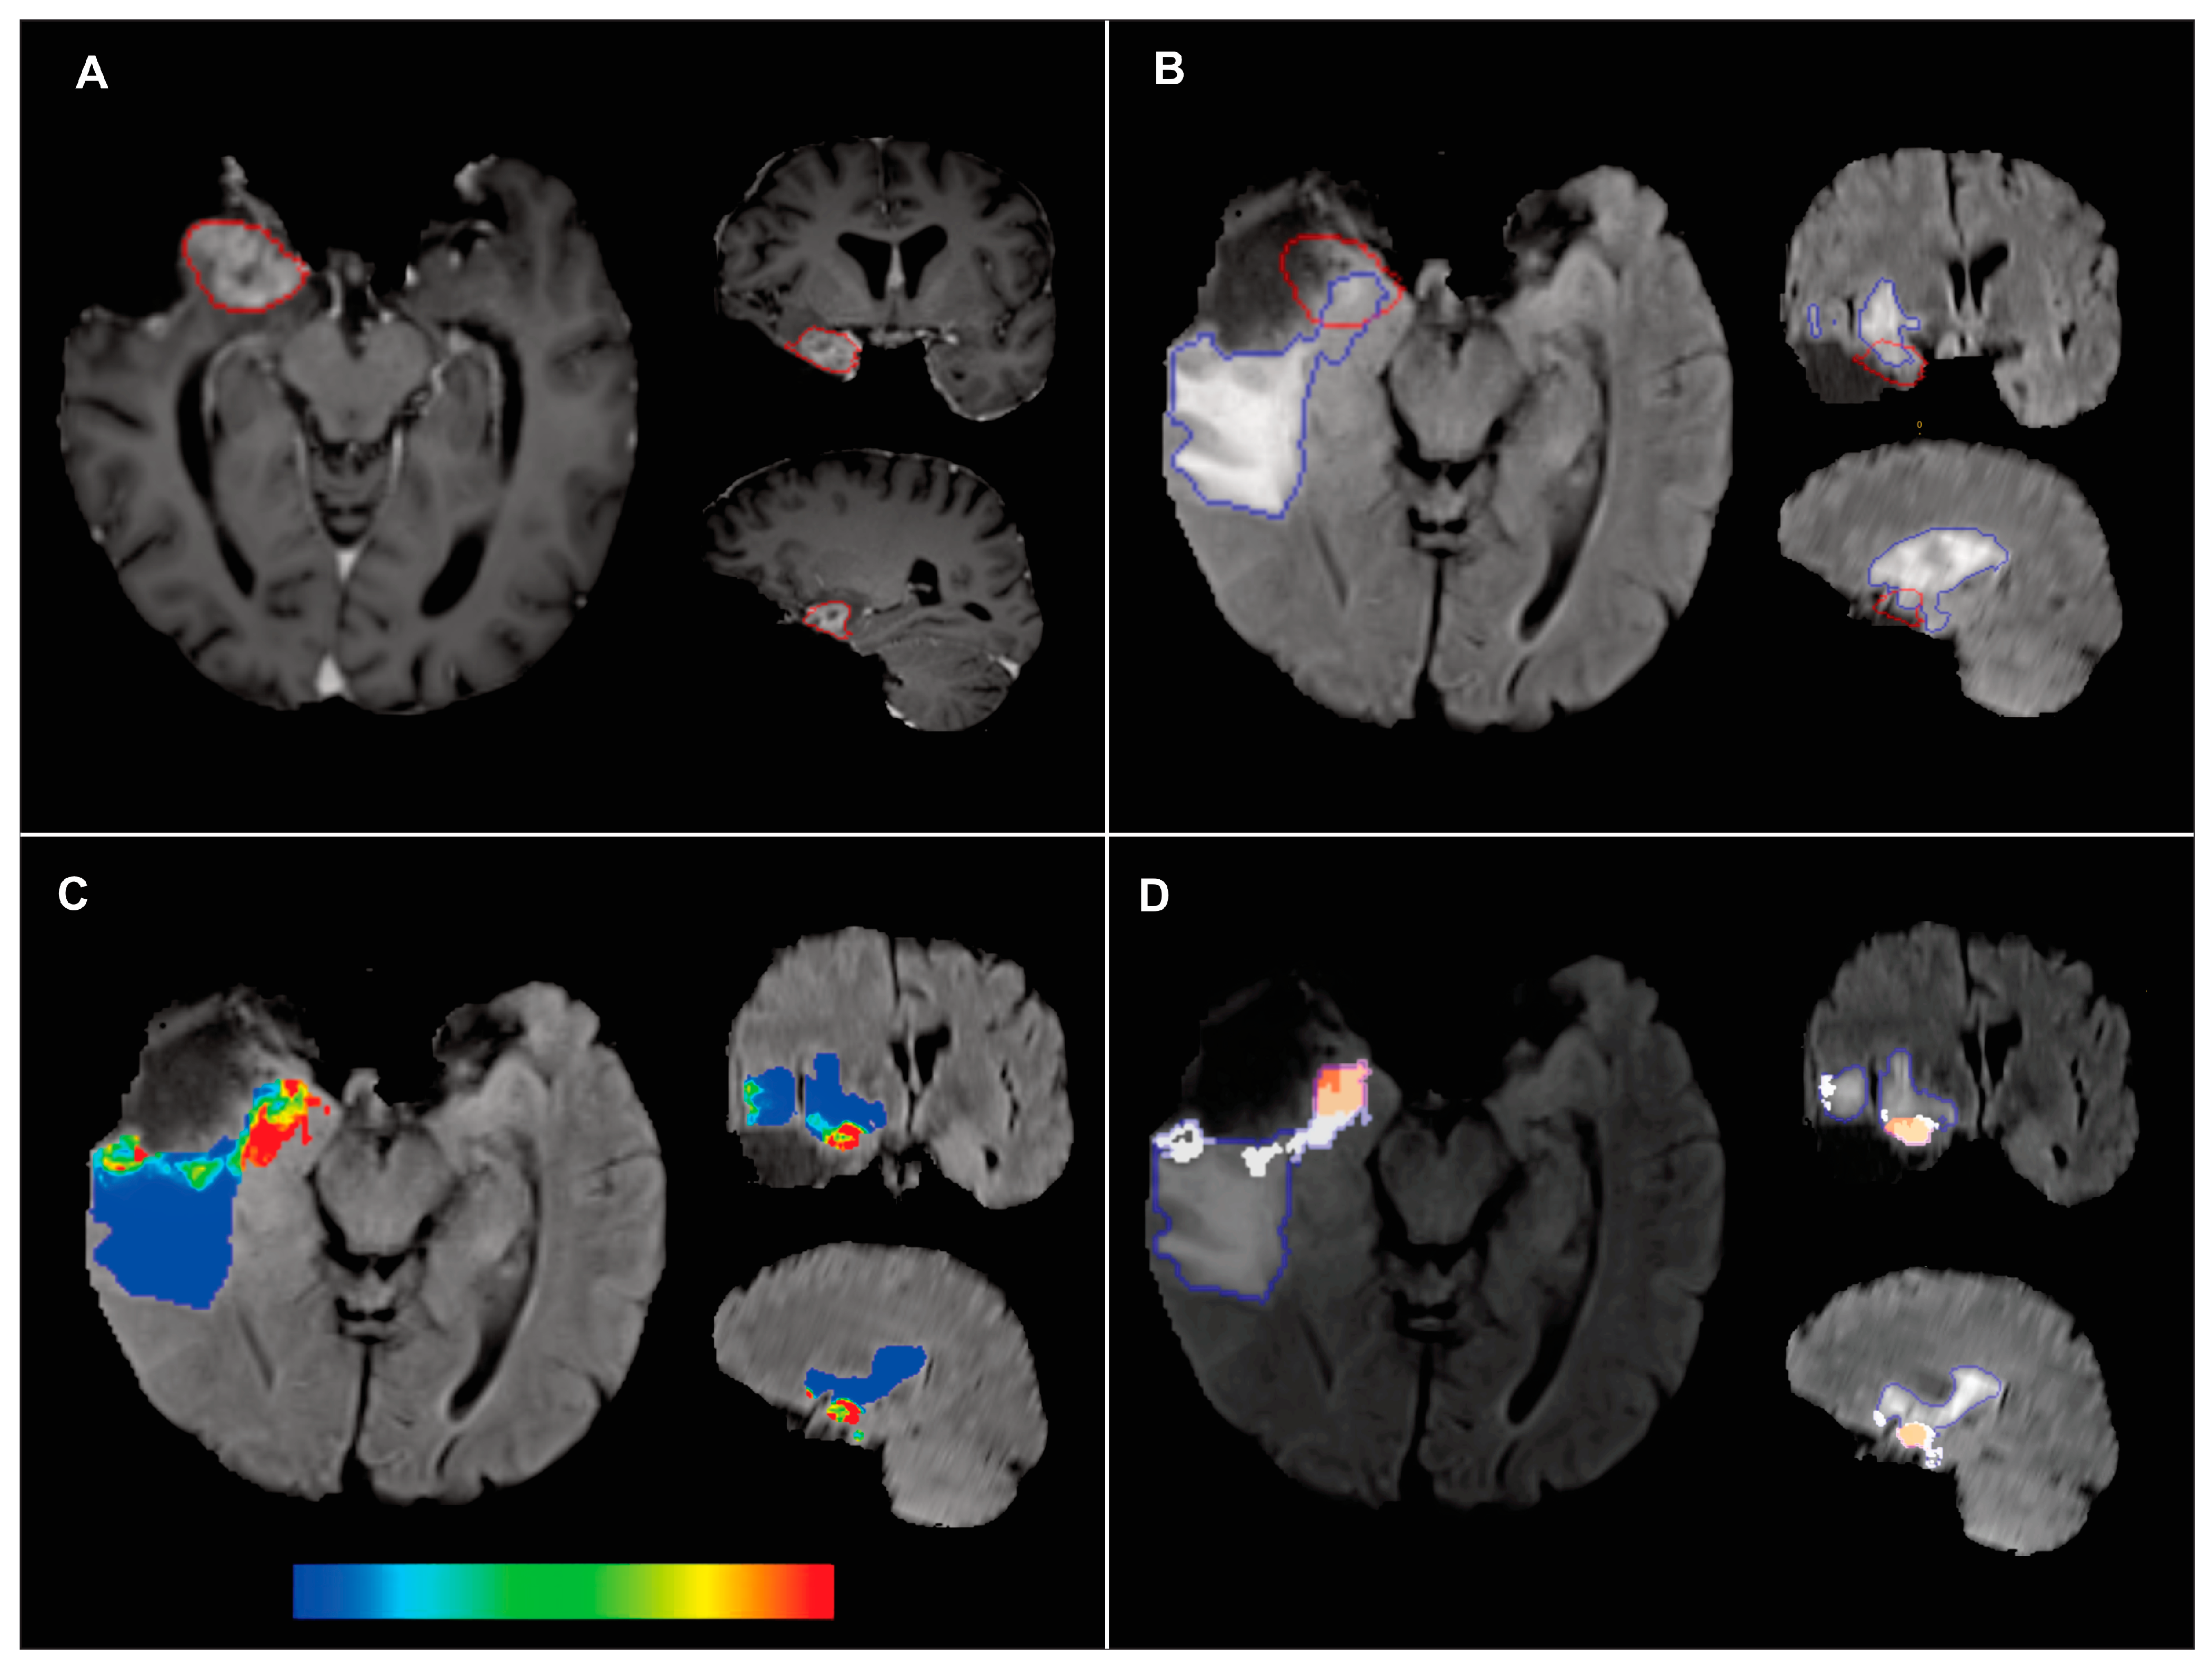

2.3. Ground Truth Segmentation

2.4. Voxel-Based Radiomic Feature Extraction

2.6. Probability Maps and Predicted Recurrence Labels